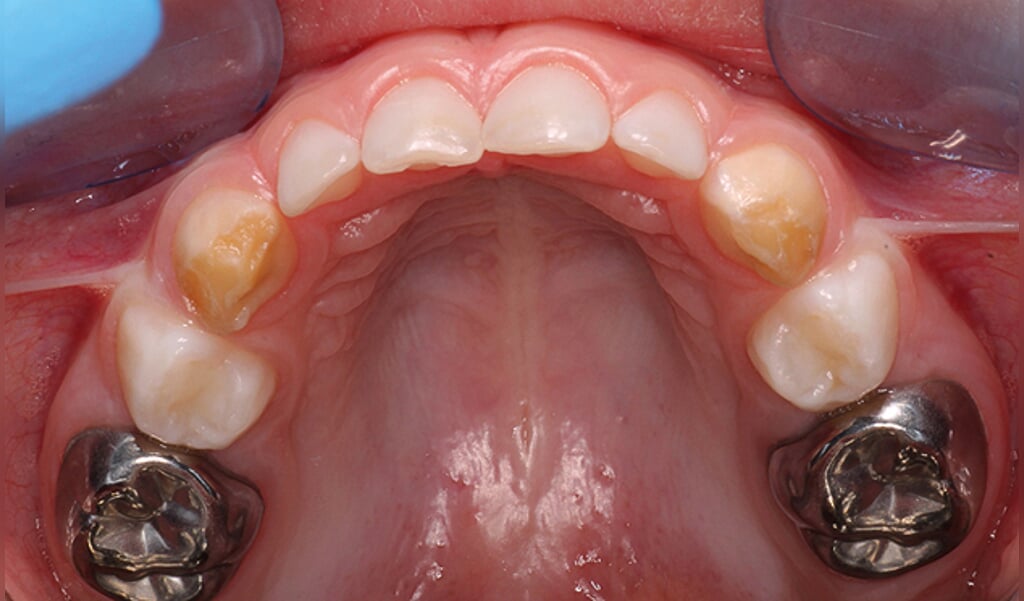

Bij kinderen is een positieve ervaring bij de tandarts essentieel voor hun verdere leven. De Hall-techniek is een innovatieve en internationaal erkende methode waarbij een metalen kroontje over een melkkies met een gaatje wordt geplaatst. Hierdoor wordt het gaatje luchtdicht afgesloten en stopt het proces, zonder dat er geboord of verdoofd hoeft te worden. Het is een snelle, pijnloze manier om de melkkies te behouden tot deze op natuurlijke wijze wisselt.

De Hall-techniek is een kindvriendelijke manier om gaatjes in melkkiezen te behandelen. In plaats van te boren, plaatsen we een roestvrijstalen kroontje over de aangetaste kies. Hierdoor wordt de bacterie afgesloten van voeding en stopt het proces van tandbederf direct.

Resultaat: De kies blijft behouden totdat deze op natuurlijke wijze uitvalt. Alleen melktanden worden behandeld.

De behandeling is pijnloos, wel voelt het kind een klein beetje druk. De meeste HALL-kronen blijven zitten tot het wisselmoment. (9-11 jaar).